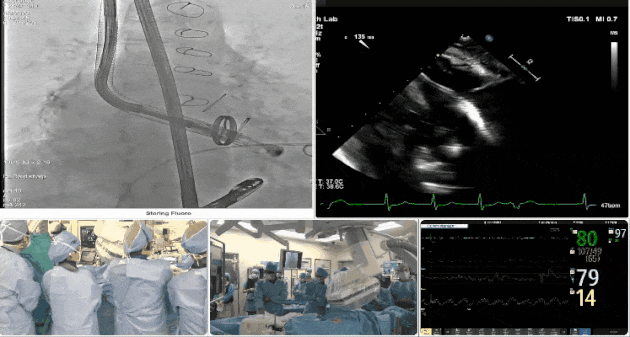

術中TEE成像困難,偽影干擾

術后DSA、超聲顯示人工瓣膜穩(wěn)定性良好,瓣葉啟閉正常,無瓣周漏